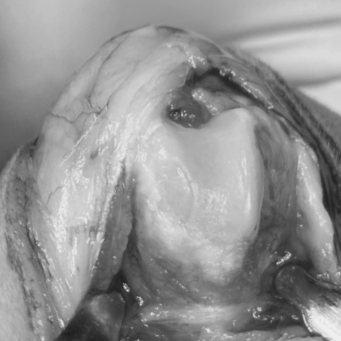

9세 뱅갈 고양이 슬개골 탈구 케이스

고양이 슬개골탈구 수술 case

방사선 촬영 시 올바른 자세로 촬영하면

탈구된 슬개골이 일시적으로 제자리로 돌아가

정상처럼 보일 수 있습니다.